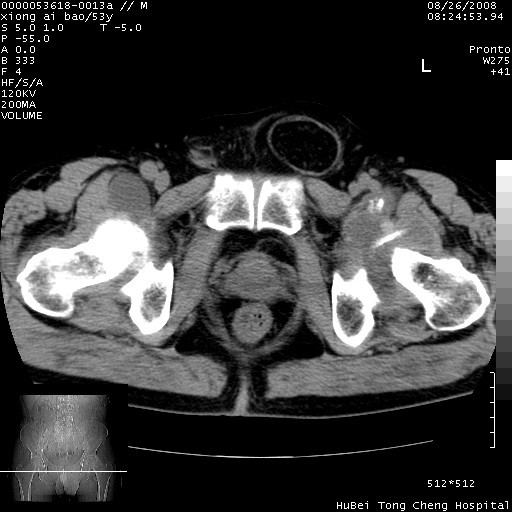

标题: CT15583:M,53Y。请老师指教分析骨盆及其他病变。 [打印本页]

标题: CT15583:M,53Y。请老师指教分析骨盆及其他病变。

双侧股骨头无菌坏死,左侧腹股沟斜疝。

非常典型病例,双侧股骨头坏死伴双髋关节周围软组织肿胀,左腹股沟疝。

双侧股骨头坏死伴双髋关节周围软组织肿胀,左腹股沟疝。

双侧骨股头无菌性坏死,左侧腹股沟疝

双侧髋关节肿胀明显,感觉还不能排除结核。

考虑双侧髋关节结核,左侧腹股沟疝